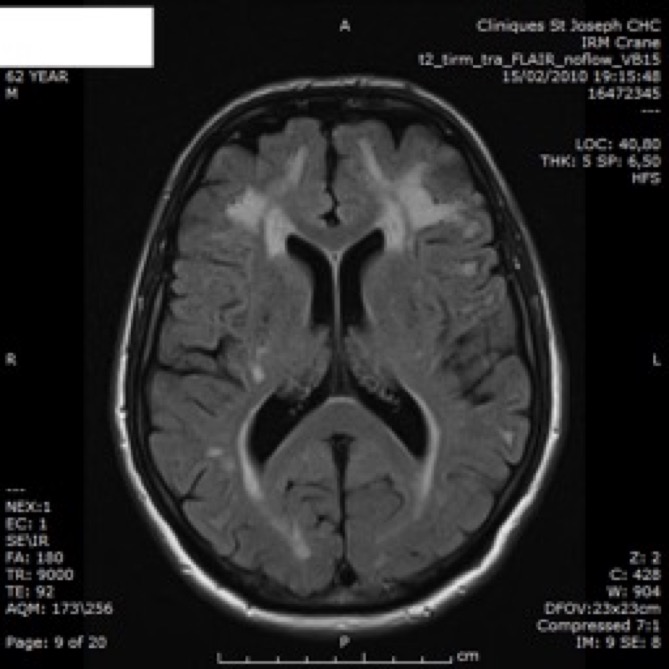

IRM

- anomalies de la substance blanche: LEP

- infarctus de petite taille, souvent profonds: sous-corticaux.